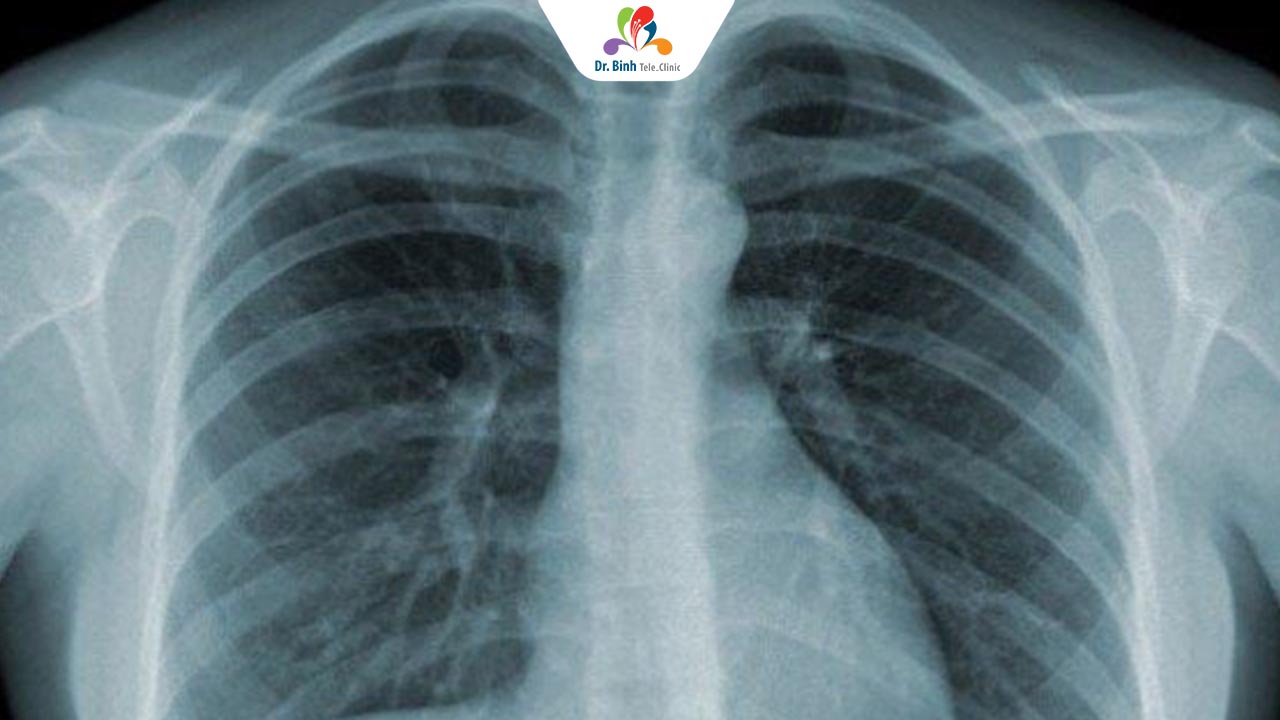

3. Chụp X-Quang hoặc CT Ngực: Giúp đánh giá mức độ tổn thương phổi và loại trừ các bệnh lý khác như ung thư phổi hoặc lao.